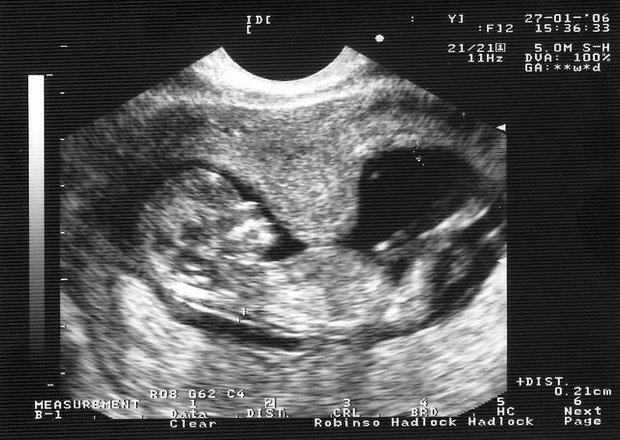

2. Ультразвуковое исследование (УЗИ)

УЗИ является одним из наиболее информативных методов диагностики. С его помощью можно не только оценить состояние матки, но и проверить, как развивается плод. УЗИ позволяет выявить признаки гипертонуса, такие как утолщение миометрия или изменение формы матки. Кроме того, с помощью УЗИ можно оценить состояние плаценты и околоплодных вод, что также важно для общего состояния беременности.